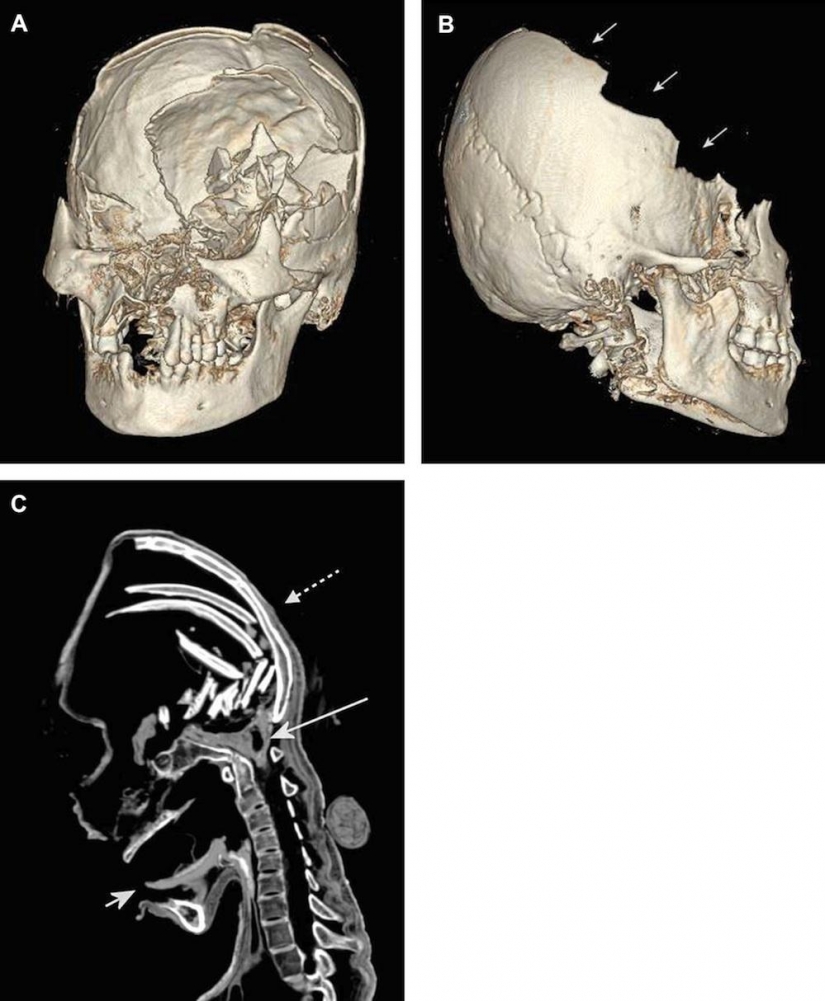

11. No hace mucho tiempo que se dio a conocer que la misteriosa momia es más que un siglo antes en la colección del Museo alemán, puede ser una mujer de la tribu de los Incas, que murió a causa de múltiples golpes en la cabeza, probablemente durante el asesinato ritual.

12. A la cabeza de la momia fueron goma de Alpacas y llamas. Se podría decir que la momia es nativa de América del Sur.

13. Su cráneo fue también característico de la "variedad" de los huesos que sólo las Naciones de América del Sur, pero no Europeos.

14. Por un lado la cara de la momia parecía bastante normal, pero en el interior de su cráneo, los huesos estaban rotos.

15. Como se puede ver, la parte frontal de su cráneo está completamente fracturado.